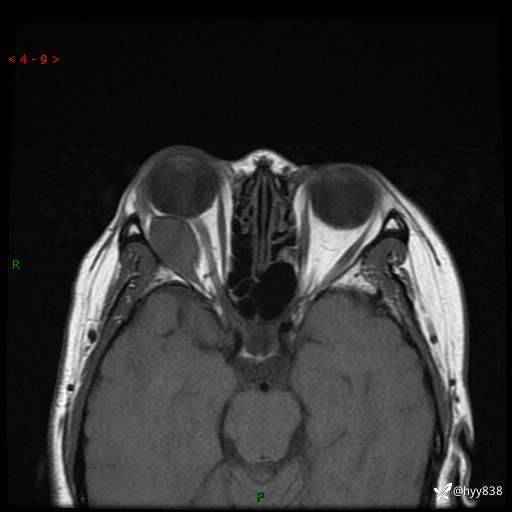

老年女性,右眼球突出1月。说说鉴别诊断,看谁第一个秒---(有结果)

主诉:发现右眼球突出1月余

简要病史:患者于1月前无明显诱因发现右眼球突出,偶感磨痛、眼胀,无视力下降,无头痛,恶心呕吐等不适。10天前就诊于当地县人民医院就诊,完善头颅ct检查,诊断为右侧眼眶肿物,建议患者上级医院进一步治疗,患者因个人原因拒绝。拟行手术,来我院就诊,门诊行相关检查后以“右眼眼眶肿物”收入院。 患病以来,患者精神饮食睡眠尚可,大小便如常、体重无明显改变。

辅助检查:MRI

临床诊断:眼眶肿物

眼眶MRI平扫+增强